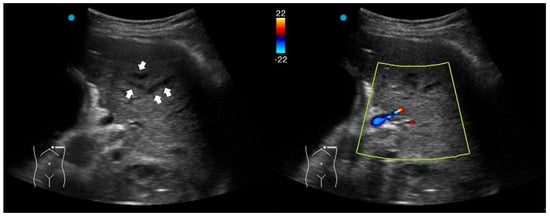

2.3. Red Flag Signs Related to Necrotizing Pneumonia

A study retrospectively reviewed 236 children with CAP. The perfusion of subpleural consolidation was classified into normal perfusion (homogenously distributed tree-like vascularity), decreased perfusion (less than 50% of an area with typical tree-like vascularity), and poor perfusion (no recognizable color Doppler flow) [28]. Poor perfusion had a positive predictive value of 100% and 81.8% for all necrotizing pneumonias and severe necrotizing pneumonias, respectively. It was also associated with an increased risk of pneumatocele formation and the subsequent requirement for surgical lung resection. However, the absence of color Doppler signals within consolidations has been scarcely studied in adult CAP and warrants further investigation in future research.

Another LUS sign of necrotizing pneumonia in children was the presence of a heterogeneous hypoechoic consolidation containing more hypoechoic confluent lesions [29]. These hypoechoic lesions were thought to correspond to necrotic cavities. Adult studies have shown that the presence of micro-abscesses or hypoechoic areas within consolidations may suggest necrotizing changes, prompting further confirmation with a repetitive CT in suspicious patients (Figure 3) [30,31].

Figure 3. Ultrasound findings in necrotizing pneumonia and corresponding computed tomography images: (A) Micro-abscesses (black arrowheads); (B) Hypoechoic lesions within consolidations (white arrowheads).